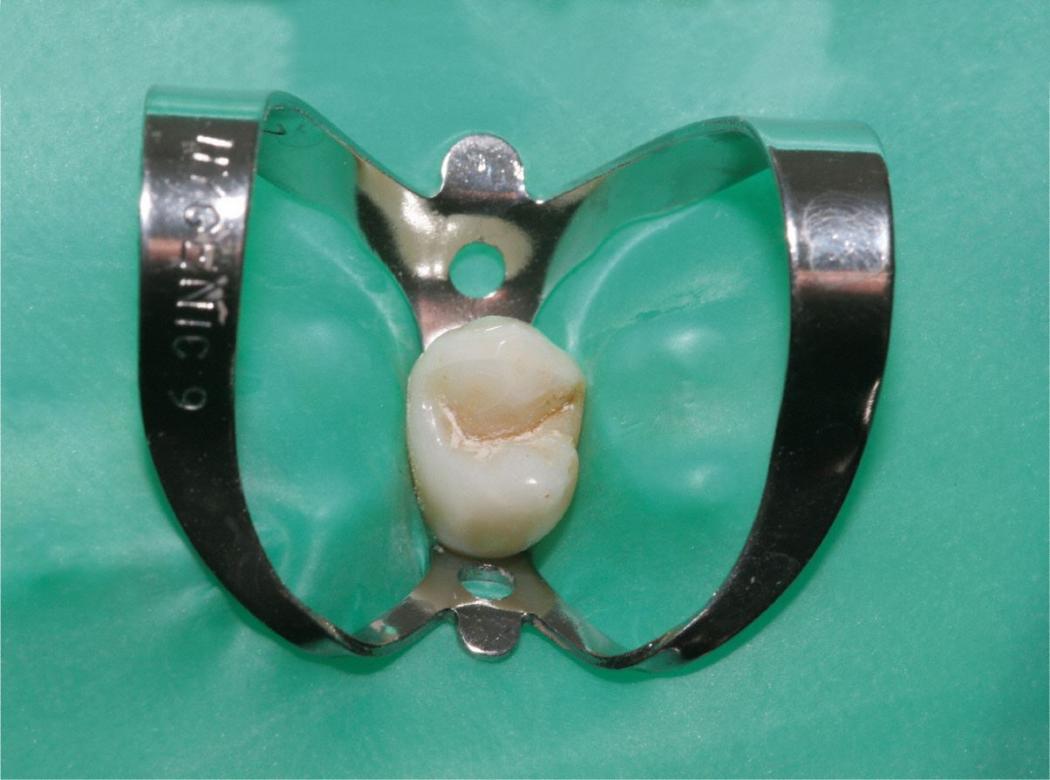

Dafür benutzt man einen speziellen Spanngummi, genannt "Kofferdam", der sowohl den Zahn isoliert, als auch das Eindringen von Bakterien aus der Mundhöhle in den Zahn verhindert. Gleichzeitig wird vermieden, dass der Patient kleine Instrumente oder Materialien verschluckt. Bild: Kofferdam